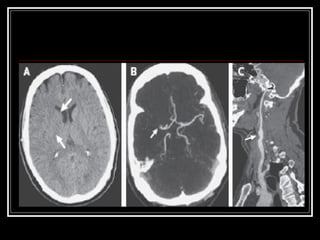

Exames de Imagem Qual a primeira escolha na emergência? Por quê? Qual o método mais sensível?

Exames de ImagemQual a primeira escolha na emergência? Por quê? Qual o método mais sensível?